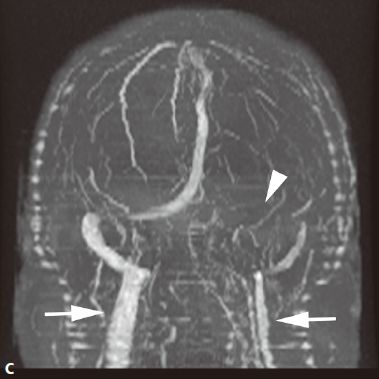

- MRA可直接显示颈内动脉、大脑前、中动脉狭窄或闭塞,于颅底见烟雾状异常血管网,常可见到颈外动脉和椎-基底动脉分支代偿性增粗。